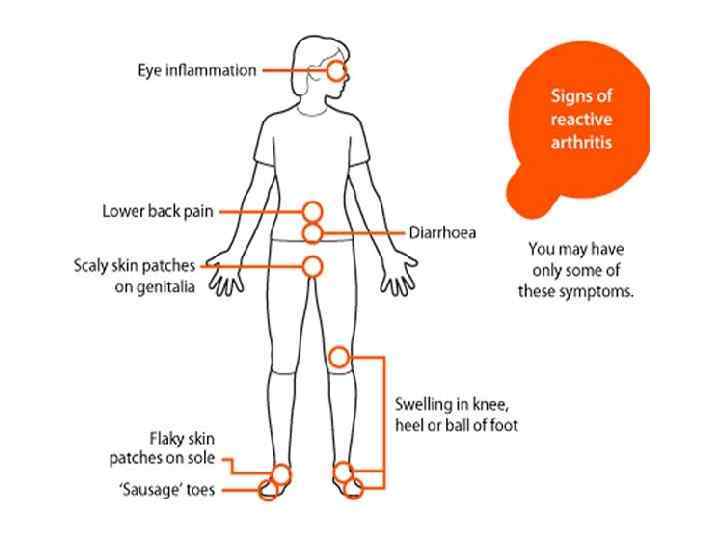

Reactive arthritis